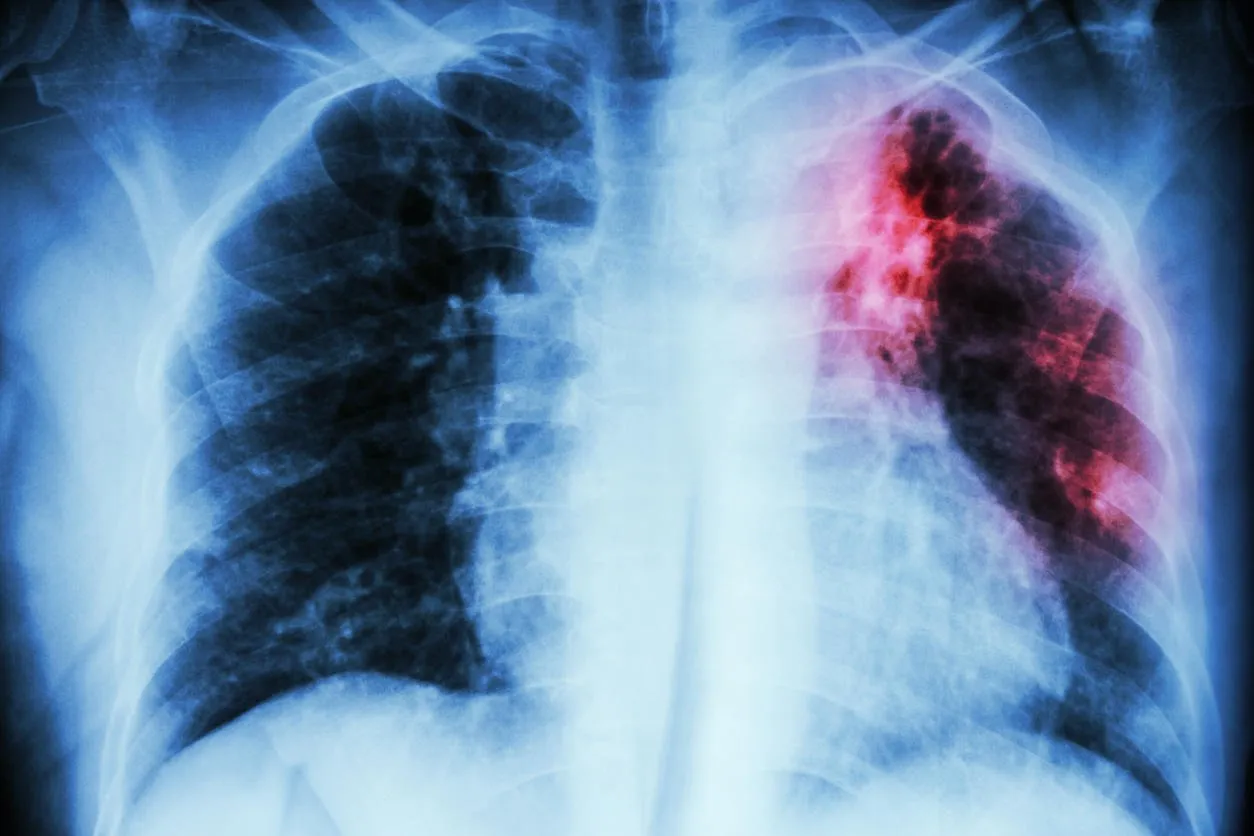

pulmonary tuberculosis  chest x-ray   interstitial infiltration at left upper lung due to mycobacterium tuberculosis infection

Fatigue et manque total d'énergie

Infections des voies respiratoires

L’hypogammaglobulinémie est une affection caractérisée par une quantité insuffisante de cellules B (globules blancs) qui fabriquent les anticorps pour combattre une infection. La baisse de ces cellules provoque la plupart du temps des infections à répétions, notamment des infections des voies respiratoires créant ainsi une insuffisance des défenses naturels de l’organisme.